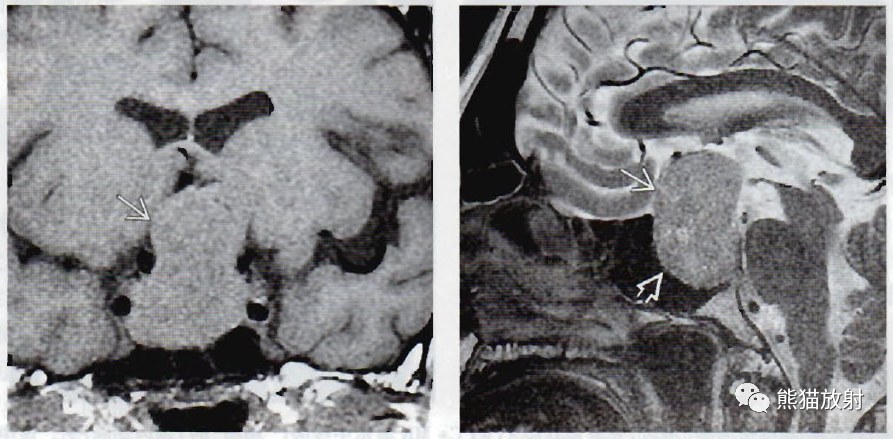

(左) 冠状位T1WI MR显示典型的“8字形”或“雪人样”垂体大腺瘤。垂体与肿块不可区分;腺体即肿块。

(右) 同一位患者,矢状位T2WI薄层扫描显示肿瘤(箭)使蝶鞍(空箭)扩大、加深。相对于灰质,肿瘤呈等信号。

(左) 一例乳腺发育、催乳素明显升高的中年男性,矢状位T1WI显示巨大的侵袭性垂体大腺瘤,侵蚀斜坡,并延伸进入蝶窦和鼻咽部。

(右) 同一患者,轴位T1WI C+MR显示肿瘤侵及并破坏斜坡。肿瘤包裹右侧颈内动脉(弯箭),但没有使其闭塞。